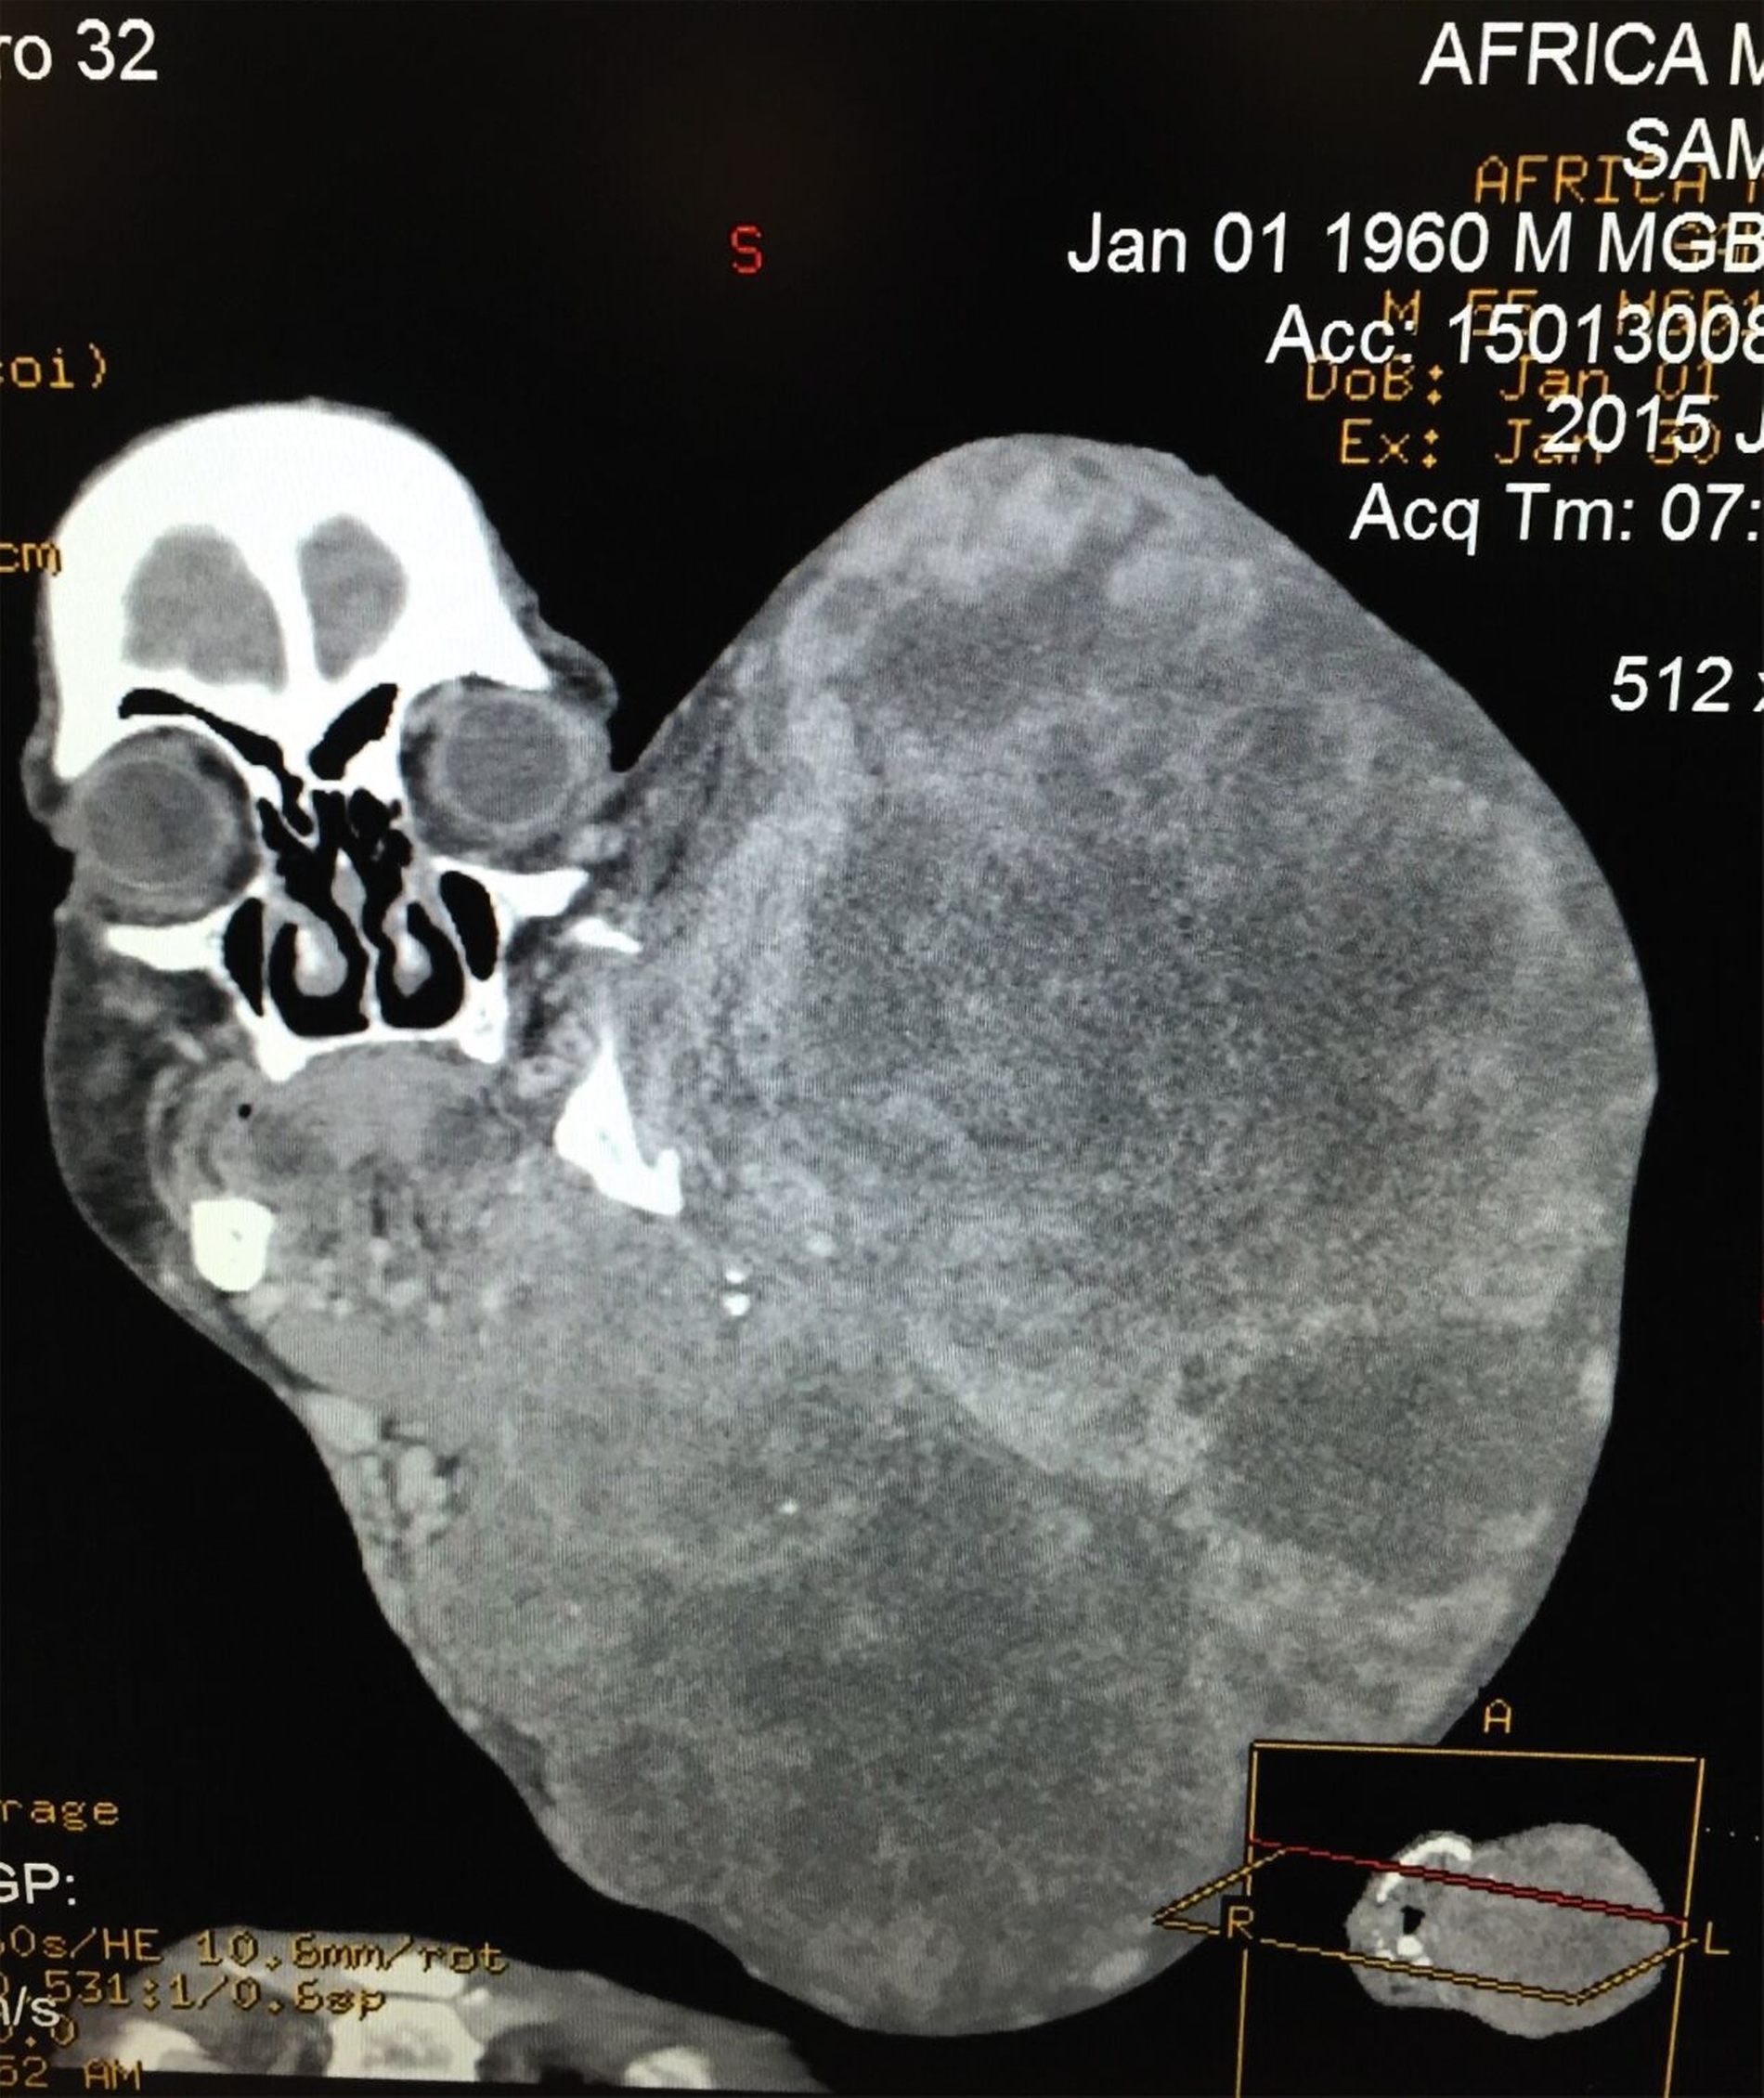

Ein prägendes Beispiel war die Entfernung eines rund acht Kilogramm schweren Gesichtstumors bei einem Mann in Madagaskar im Jahr 2015. Der Eingriff dauerte zwölf Stunden und erforderte das gesamte chirurgische, anästhesiologische und pflegerische Team – und 17 Crew-Mitglieder, die spontan Blut für die notwendigen Transfusionen spendeten. Das war ein Moment, der den Geist dieser Missionen in besonderer Weise widerspiegelt!